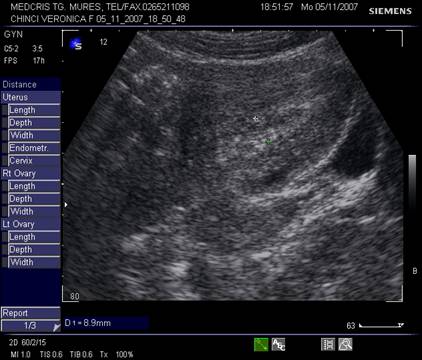

Ecografic, dispozitivul apare ca o structura ecogena cu forma variabila, localizat alaturi deasupra sau sub sacul gestational, eventual in canalul cervical.